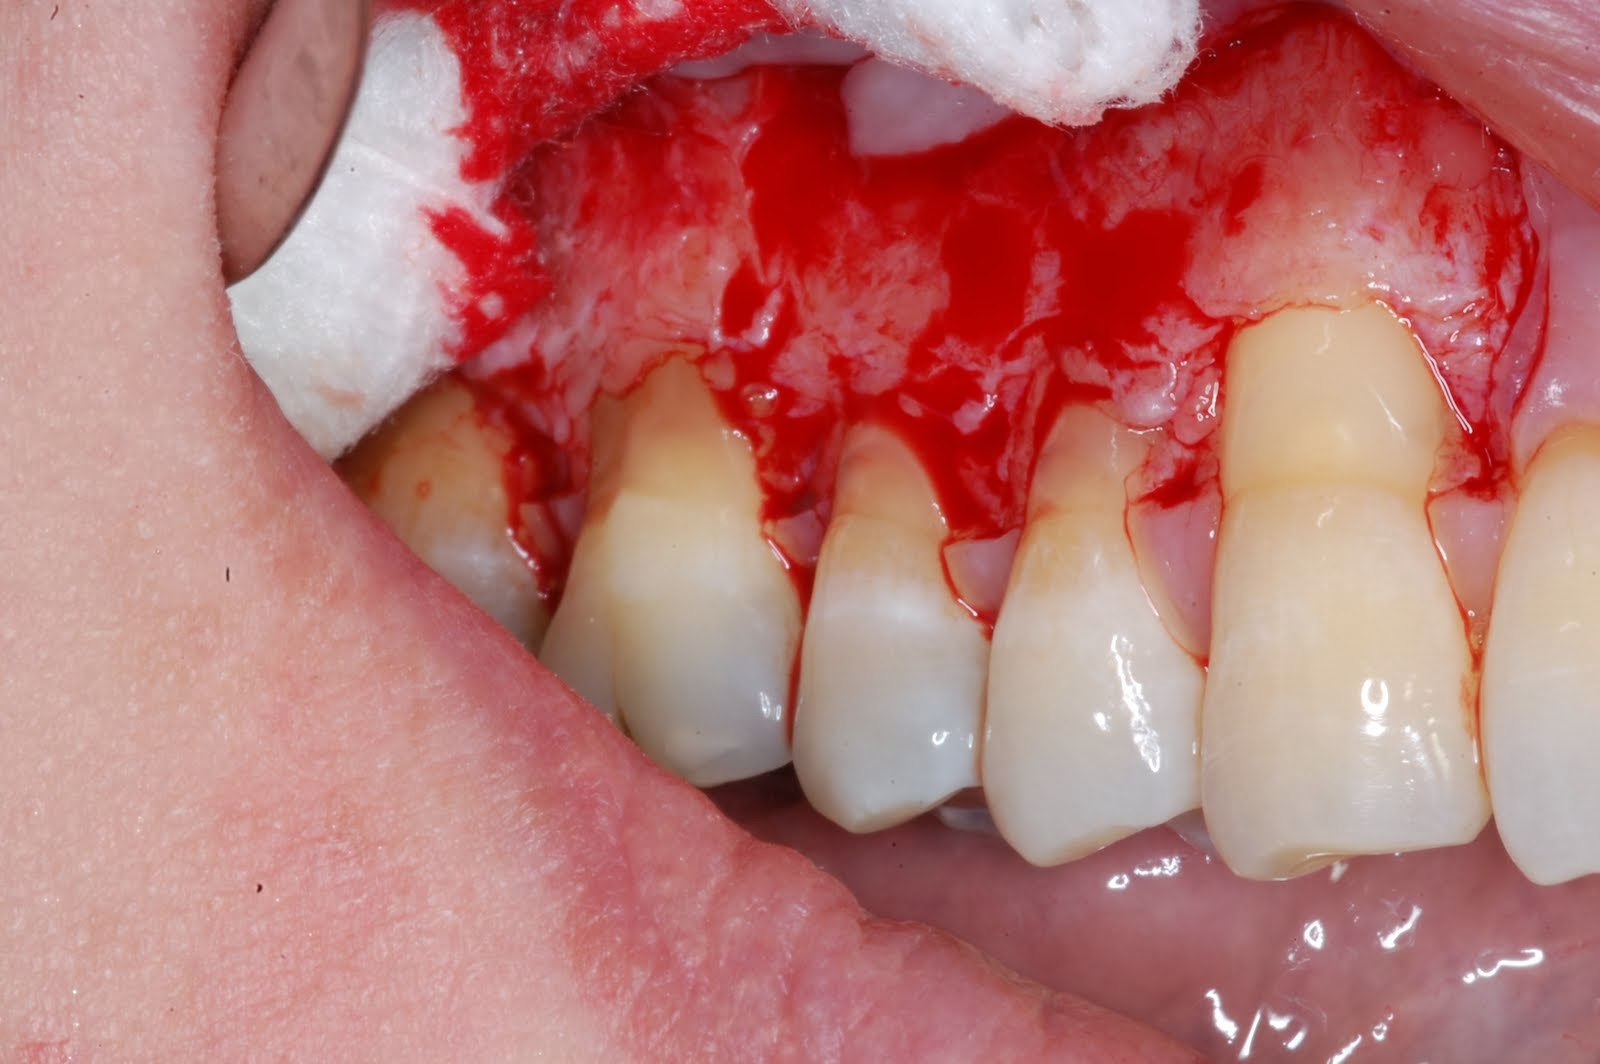

На фотографии продемонстрирована тяжелая форма периодонтита с кровоточащими деснами.